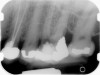

Clinical procedure: If apical bone loss is present (Figure 1) a collagen/gelatin sponge (eg, Gelfoam®, Pfizer Inc., www.pfizer.com) can be placed apically so that the MTA can be delivered to the desired working length. (Any other surgical resorbable sponge would also work, such as OraPlug® [Salvin Dental Specialties, www.salvin.com], Surgifoam® [Midwest Dental, www.mwdental.com], or Surgispon® [Aegis Lifesciences, www.surgispon.com]). This is done by taking a small piece (2 mm x 2 mm) of the resorbable sponge and pushing it down to and through the root apex with an endodontic file. Once this is done, MTA is packed down the canal with a custom-fitted cone. The clinician can use a rubber stopper on the gutta-percha cone to know the exact length of MTA placed in the apical third (Figure 2). Once the apical third is sealed with 3 mm to 5 mm of MTA, the remaining coronal canal space can be back-filled using a warm gutta-percha technique (Figure 3).